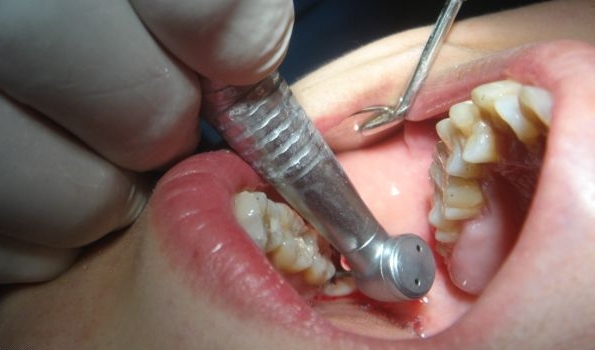

补牙为什么越早越好 如果患了龋病就应尽可能地早修补,因为龋洞经过修补后可以阻止龋病病变的发展,及早恢复牙齿的功能,保持牙列的完整若不进行及时治疗,病变就会越来越大,从浅龋发展到深龋... 补牙 范姜英杰 569 2023-11-25